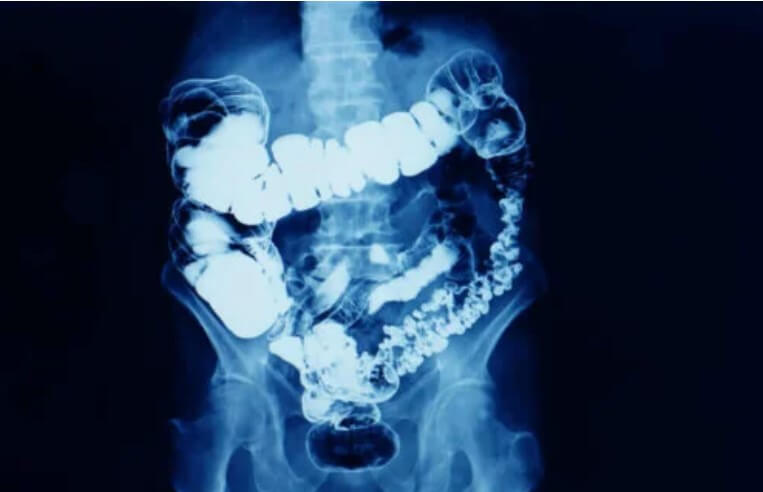

Γενικά, η δυσκοιλιότητα είναι όταν μειώνεται η συχνότητα των κοπράνων. Η δυσκοιλιότητα είναι ένα σύμπτωμα που σημαίνει ότι η εντερική διέλευση μειώνεται για κάποιο λόγο.